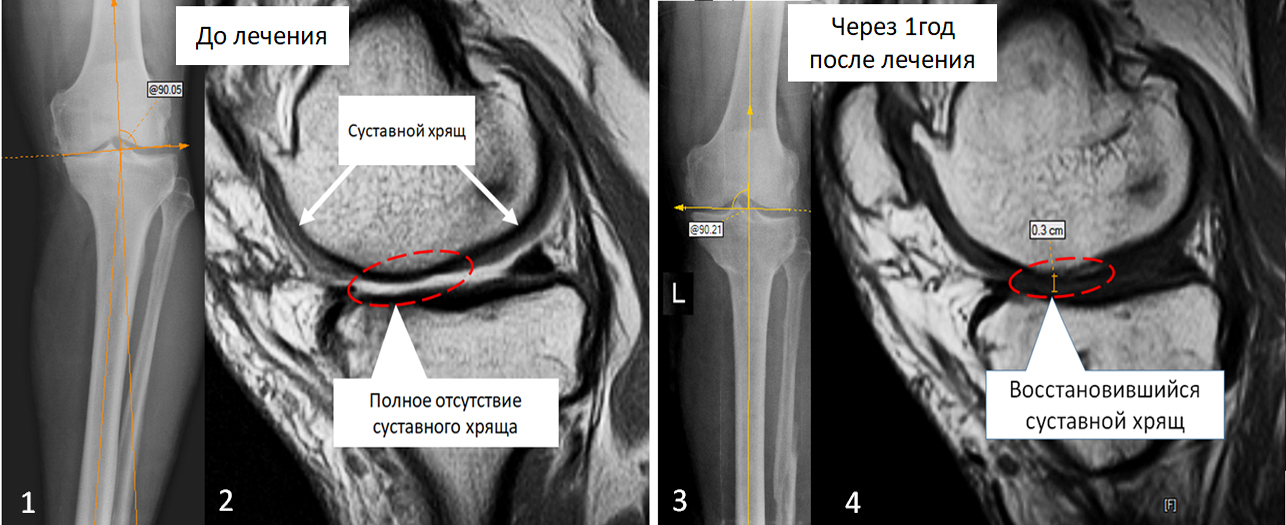

До початку лікування на рентгенограмі (1) - виражена варусна деформація великогомілкової кістки. На МРТ знімках (2) - є ділянка суглобової поверхні з повною відсутністю суглобового хряща (обведено пунктирною лінією), на місці хряща визначається суглобова рідина. У нормі суглобовий хрящ виглядає як широка сіра смуга (вказано стрілками).

Ми провели відновне оперативне лікування з використанням аутологічних мезенхімальних стовбурових клітин.

Через один рік після оперативного лікування. На рентгенограмі (3) - вісь великогомілкової кістки відновлена. На МРТ знімках (4) - на місці відсутнього раніше суглобового хряща утворився новий хрящ товщиною до 3 мм (обведено пунктирною лінією).